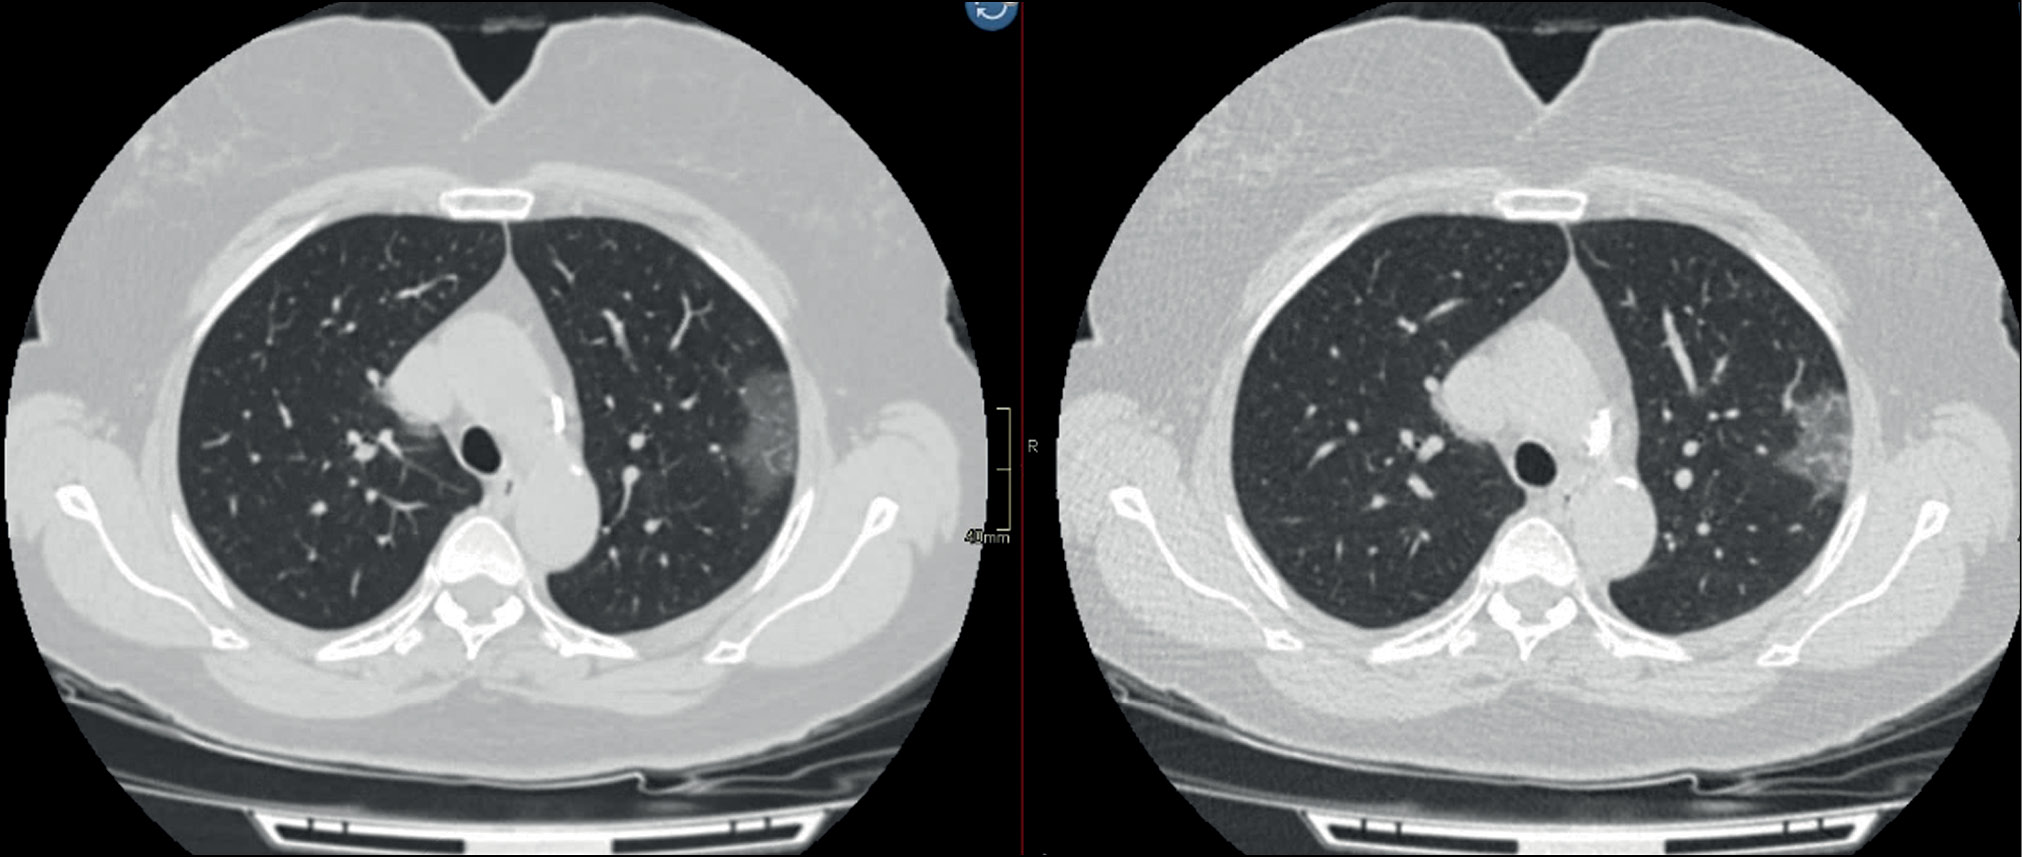

Any special low-dose protocols require clinical validation and comparison with the gold standard. Therefore, clinical trials of the developed LDCT protocol for COVID-19 used standard CT as a reference technique. [28] Some of the clinical images obtained using the developed protocol are shown in Figs. 2 and 3.

Figure 2. Radiation exposure is reduced by 5 times. Patient, 59 y. o., BMI 29 kg/m2. Computed tomography with a soft tissue filter (effective dose: 9.7 mSv), low-dose computed tomography with a soft tissue filter (effective dose: 2.1 mSv). In the upper lobe of the left lung, there was a peripheral ground-glass lesion.